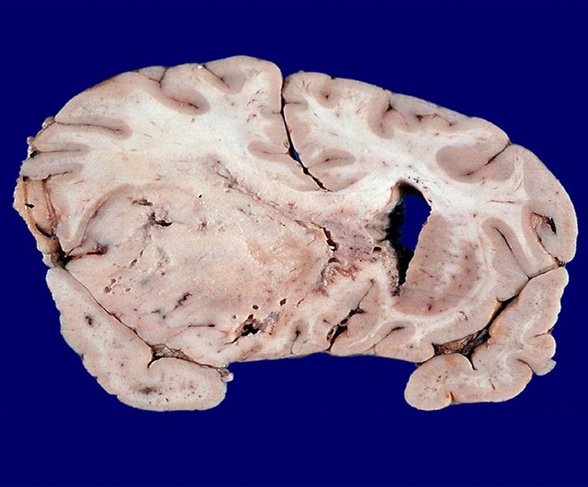

Lots of hemorrhaging, weak blood vessels, and necrosis growing fast

GBM

pleomorphic astrocytes

mitotic activity

vascular proliferation here

necrosis

know this picture!

Palisading neoplastic cells surrounding necrosis

GBM grade 4 astrocytoma

Geographic pattern, a perimeter of neoplastic glial cells surrounding necrosis